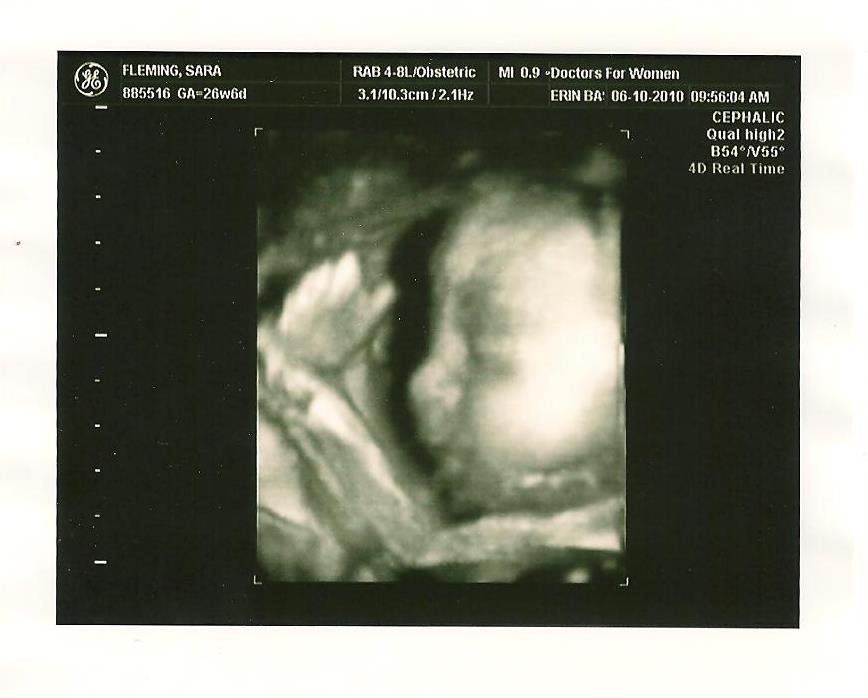

"Everybody says I look just like my Daddy. I have his nose and profile. But, I also have Mommy's cheeks and rounder face!" "I was not happy here. Mommy couldn't eat for 12 hours because of her glucose test, and the ultrasound tech. kept poking me to get me to turn. I don't usually play or kick at this time of day!"

"I was not happy here. Mommy couldn't eat for 12 hours because of her glucose test, and the ultrasound tech. kept poking me to get me to turn. I don't usually play or kick at this time of day!" "I really look like Daddy here! I was practicing sucking in and poking my lips out. Mommy was hoping I'd suck my thumb, but I didn't this time."

"I really look like Daddy here! I was practicing sucking in and poking my lips out. Mommy was hoping I'd suck my thumb, but I didn't this time." " They finally got me to turn a little bit, but I was still very shy and sleepy. I kept putting my hands over my eyes."

" They finally got me to turn a little bit, but I was still very shy and sleepy. I kept putting my hands over my eyes." "No more photographs, please! I know I'm so adorable, but you'll just have to wait to see me until I come out in a few month." :)